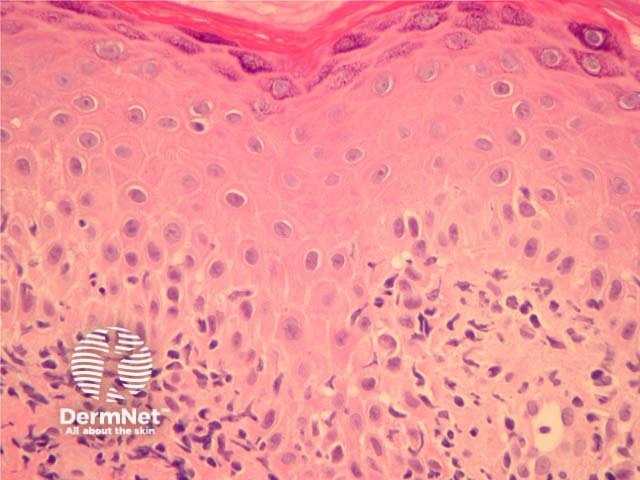

Chilblain lupus erythematosus: Frank lymphocytic vasculitis and interface changes are more common in chilblain lupus than in idiopathic chilblains (figure 5). A positive antinuclear antibody test favours chilblain lupus erythematosus.